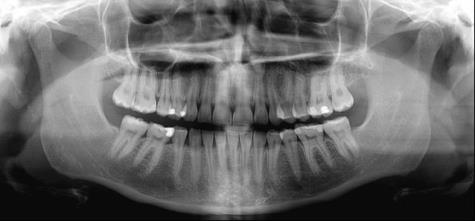

Koko leuan hammasröntgen on hammashoidon perustutkimus, joka kuuluu ottaa silloin, kun kuvantamiseen löytyy riittävä peruste. Hammaslääkärin kuuluu selvittää aina röntgenkuvauksen yhteydessä kuvauksen syy ja kertoa potilaalle, millainen kuvaus on riittävä suun tilanteen oikean diagnoosin saamiseksi.

Yleisimpiä kuvausvaihtoehtoja ovat pikkukuvat yksittäisistä hampaista tai koko leuan kuvantaminen. Näiden perusteella on mahdollista päättää, onko epäilyttäviä alueita tarvetta tarkentaa 3D-tomografiakuvauksella. Näiden kaikkien kuvausmenetelmien säteilyannokset ovat alhaisia.

Kuvantamisella voidaan selvittää yleisimmin ientulehduksen aiheuttamaa luukatoa, kariesta, hampaiden juurenkärkien alueiden tulehduksia ja viisaudenhampaiden tilanne. Koko leuan kuvasta hammaslääkäri näkee suun hoitohistoriaa. Näin saadaan tietoa hoidon suunnittelua varten.

Panoraamakuvat paljastavat yllättäviä löydöksiä

Hampaiston ja leukojen panoraamakuvausta selvittävässä väitöskirjatutkimuksessa hammaslääkäriä pyydettiin kirjaamaan jokaisen koko leuan hammaskuvauksen yhteyteen tarkka syy, miksi kuvaukseen päädyttiin. Selvisi, että lähes 70 prosenttia kuvista paljastaa suusta yllättäviä löydöksiä eli jotakin muuta, kuin miksi kuvaus on alun perin tehty.

Potilaalla voi olla särkyä ylhäällä vasemmalla, mutta koko leuan röntgenkuva paljastaa suun muilla alueilla olevaa kariesta. Tai jos suu kuvataan tietyn hampaan poistoa suunniteltaessa, tulehduksia löydetään aivan toiselta puolelta suuta. Hammaslääkäri joutuukin aina pohtimaan tapauskohtaisesti, onko potilaan edun mukaista ottaa koko leuan kuva yksittäisen hampaan sijaan.